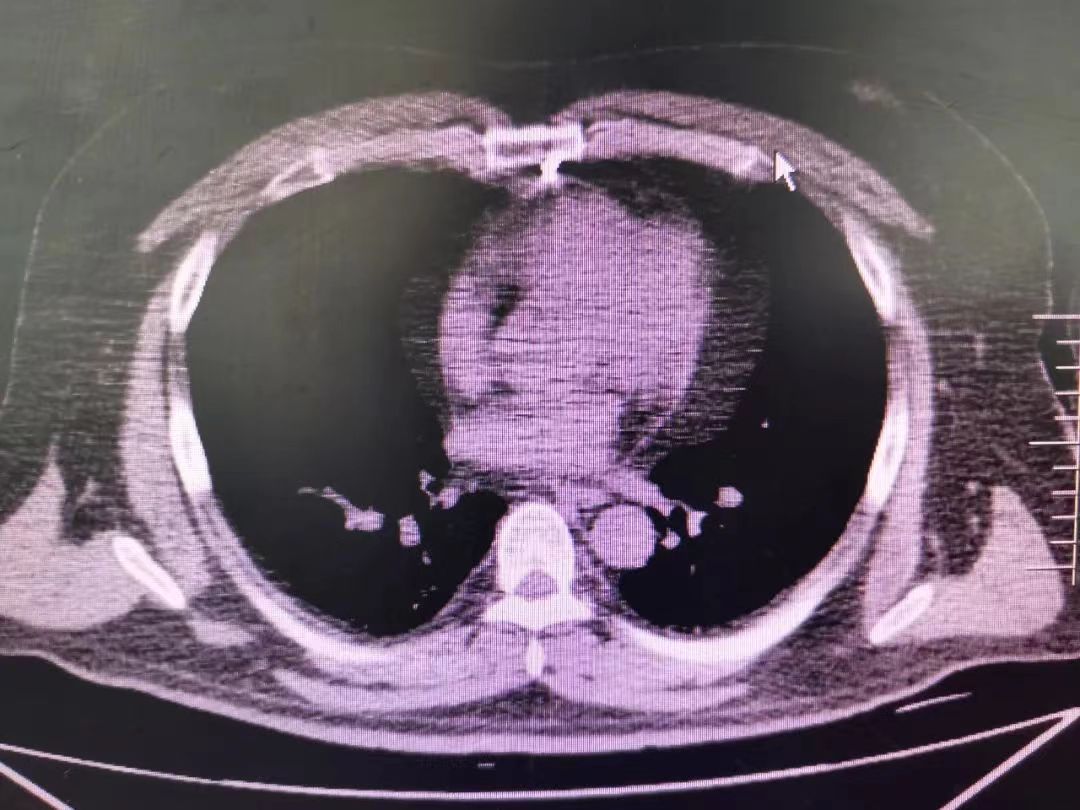

查看病人病情及CT后,考慮到刀尖離心臟較近,隨時有加重損傷的可能,武小剛主任當機立斷,將拔了剪刀向外拔出約5mm,局部固定,避免遂呼吸或搬動患者造成進一步損傷心臟。因患者病情特殊,術前、術中不可預知風險較多,武小剛主任與麻醉科醫師溝通后,分析病情:“手術患者剪刀斜著刺入,有損傷肋間及乳內動脈可能,故需全麻下手術拔除,萬一已傷到胸壁血管,那就需要開胸止血,否則大出血會導致患者休克而死亡;如拔出后出血少,動態觀察后可不劈開胸骨,減少了對患者更大的損傷,也能保住患者的生命,其次手術需打破傷風抗毒素及預防使用抗生素,減少術后感染的風險”。術中,對插入剪刀周圍進行嚴格消毒,徹底游離周圍組織,避免出血而無法準確定位止血,隨后小心翼翼的將剪刀拔除,骨面可見少量出血,觀察半小時未見明顯出血,血壓平穩,手術順利,這才松了口氣。術后1小時左右患者清醒,哽咽著對武主任及科室醫護人員說:“謝謝醫生,謝謝你們,真的,真的太感謝了,不瞞您說,后事我已經跟家人交代過了……”。武主任輕拉患者的手說:“你真是不幸中的萬幸啊,差一點你就沒機會來醫院了,也別緊張了,再恢復恢復就回家,以后多注意”。術后監測生命體征,第二天拔除引流管,按時換藥,復查心臟彩超、胸部CT,未見異常于1周后痊愈出院。